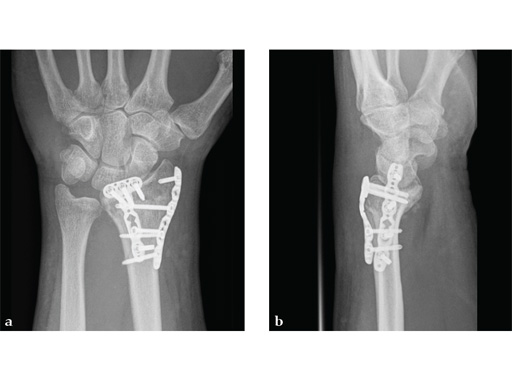

Case 1: A 62-year-old man fell on his outstretched left hand while playing tennis, sustaining an intraarticular fracture of the distal radius, Mller AO Classification 23-C3.2.

Case provided by Renato Fricker, Bruderholz, Switzerland